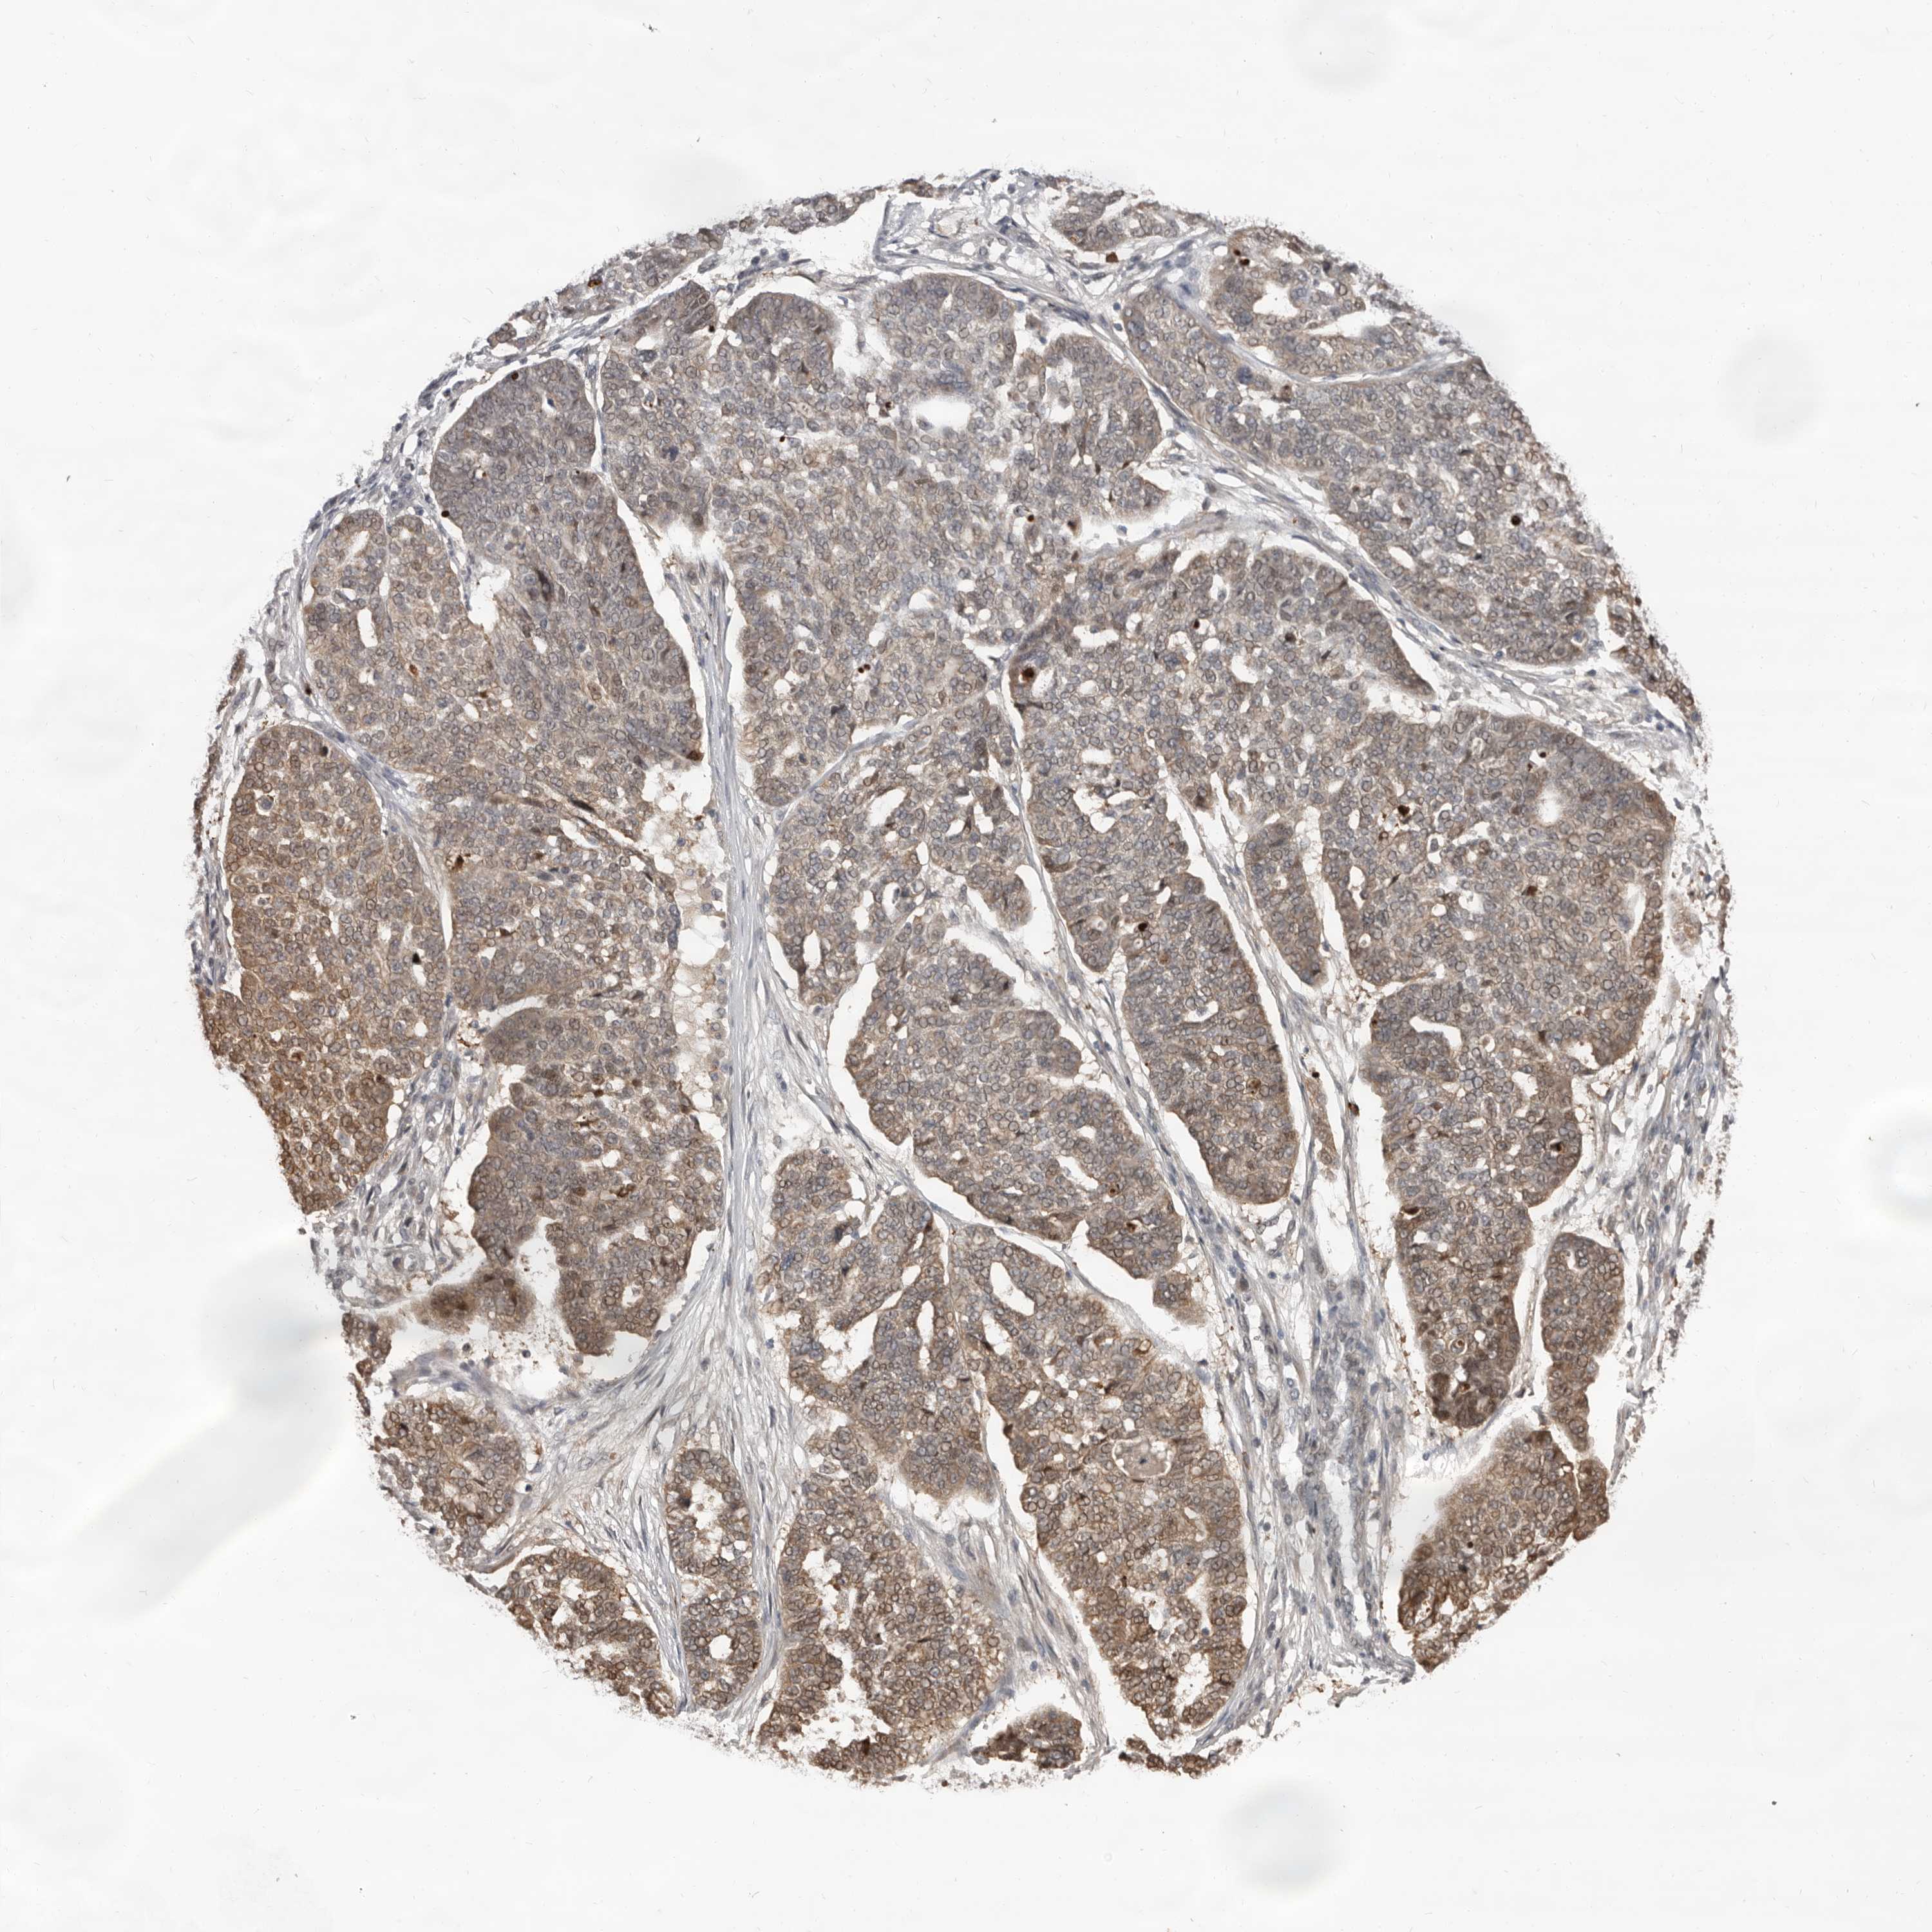

OVARIAN CANCER - Protein expressioni

A mouse-over function shows sample information and annotation data. Click on an image to view it in a full screen mode. Samples can be filtered based on level of antibody staining by selecting one or several of the following categories: high, medium, low and not detected. The assay and annotation is described here.

Note that samples used for immunohistochemistry by the Human Protein Atlas do not correspond to samples in the TCGA dataset.

Antibody stainingi

Antibody staining in the annotated cell types in the current human tissue is reported as not detected, low, medium, or high, based on conventional immunohistochemistry profiling in selected tissues. This score is based on the combination of the staining intensity and fraction of stained cells.

Each image is clickable and will lead to virtual microscopy that enables deeper exploration of all samples and also displays staining intensity scores, fraction scores and subcellular localization as well as patient and tissue information for each sample.

Antibody HPA029165

Antibody HPA029167

Antibody CAB028574

Staining

High

Medium

Low

Not detected

Intensity

Strong

Moderate

Weak

Negative

Quantity

>75%

75%-25%

<25%

None

Location

Nuclear

Cytoplasmic/membranous

Cytoplasmic/membranous,nuclear

Cystadenocarcinoma, serous, NOS

Carcinoma, endometroid

Cystadenocarcinoma, mucinous, NOS

Carcinoma, NOS